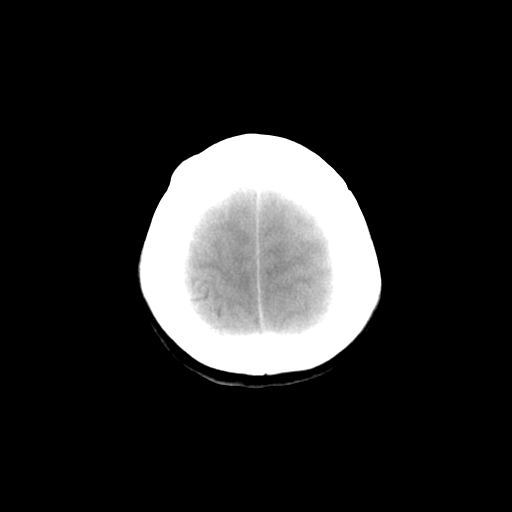

标题: CT14513:女性41岁,头部不适二月余,其它病史不详。请分析 [打印本页]

标题: CT14513:女性41岁,头部不适二月余,其它病史不详。请分析

1.考虑:左侧颞顶叶星形细胞瘤。2.大脑镰下疝。

支持!但楼主所提示处颅骨明显受压变薄,是否有合并蛛网膜囊肿或局部硬膜下水瘤的可能?脑穿通畸形暂不予以考虑:明显占位表现;病侧脑室无扩张;病灶不是较明确的脑脊液密度;边界不清晰。还是mri检查吧,提供的有价值信息更多一些,至少可以排除或肯定蛛网膜囊肿或局部硬膜下水瘤的存在。

1)考虑左侧颞顶叶胶质瘤。2)左侧颞顶部慢性硬膜下血肿?3)大脑镰下疝。